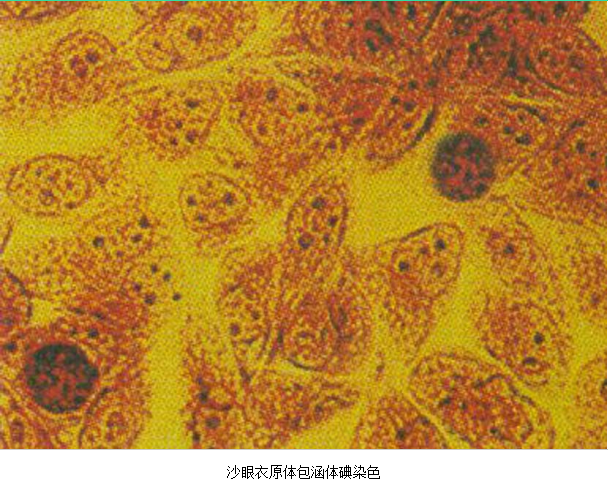

3.病原体检测 应作衣原体及淋病奈瑟菌的检测,以及有无细菌性阴道病及滴虫阴道炎。检测淋病奈瑟菌常用的方法有:①分泌物涂片革兰染色,查找中性粒细胞内有无革兰阴性双球菌,由于子宫颈分泌物的敏感性、特异性差,不推荐用于女性淋病的诊断方法。②淋病奈瑟菌培养,为诊断淋病的金标准方法。③核酸检测,包括核酸杂交及核酸扩增,尤其核酸扩增方法诊断淋病奈瑟菌感染的敏感性及特异性高。检测沙眼衣原体常用的方法有:①衣原体培养,因其方法复杂,临床少用。②酶联免疫吸附试验检测沙眼衣原体抗原,为临床常用的方法。③核酸检测,包括核酸杂交及核酸扩增,尤以后者为检测衣原体感染敏感、特异的方法。但应做好质量控制,避免污染。